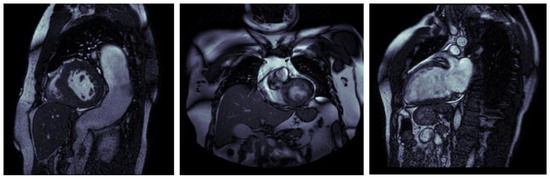

- We used rotational augmentation to rotate photos at 90-, 180-, and 270-degree angles, depicted in Figure 4. This geometric modification not only increased the size of our dataset by 3 times but also created useful variations in orientation, increasing the information available to our models. We only intended to spin the MRIs at four angles because rotating an MRI to a random degree between those mentioned above would not be realistic because the patient is not in a 15 degree position during the exam, for example. This creates 606 new MRIs out of the original dataset.